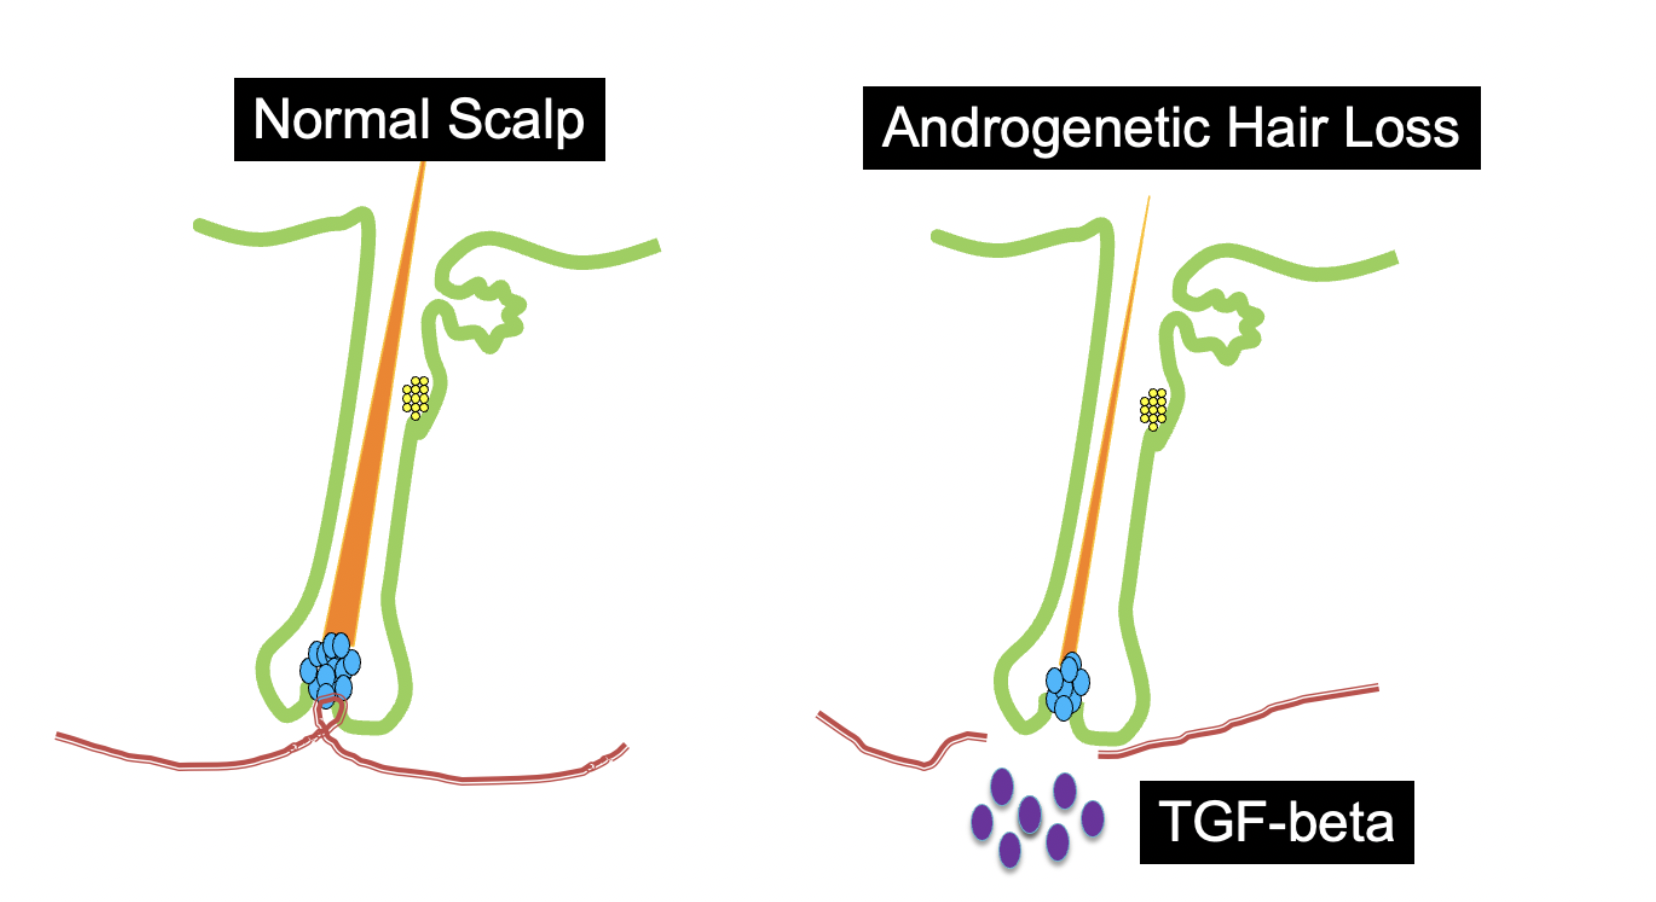

I have reviewed before the AGA is associated with an early disappearance of blood vessels in the dermal papillae of hair follicles.

A 2022 study by Deng and colleagues showed that early balding is associated with a disappearance of the tiny blood vessels in the dermal papilla. Photo: Donovan Hair Clinic 2022. Study Referenced: Deng et al. Androgen receptor-mediated paracrine signaling induces regression of blood vessels in the dermal papilla in androgenetic alopecia. J Invest Dermatol. 2022